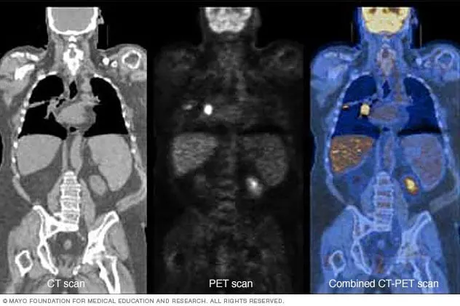

What Is a PET-CT Scan?

A PET-CT scan combines metabolic imaging from a PET scan with the structural detail of a CT scan, offering a more comprehensive diagnostic picture.